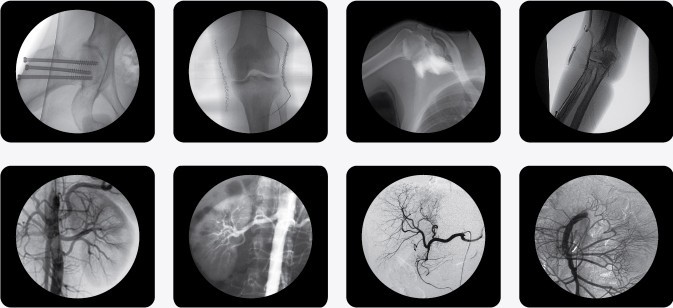

近幾年,我國醫(yī)療設備市場可謂一片欣欣向榮,不少醫(yī)療器械廠家紛紛崛起,在不少領域打破了進口醫(yī)療設備壟斷的局面,C行臂X射線機就是其中之一。國產移動三維C行臂X射線機的崛起,給國內醫(yī)療單位也帶來了很大的便利,不僅節(jié)約了大量的成本同時售后也有了更大的保障。目前國產三維骨科C行臂X射線機與進口機器并無差異,國產大型三維骨科C行臂X射線機經銷商有不少,普朗醫(yī)療旗下的南京普愛影像有限公司就是其中的優(yōu)秀者之一。本公司最新推出的具備DSA的中C,一經推出就在國內C臂市場刮起一股C臂提升檔次的旋風,到目前為止全國市場中級醫(yī)院都在考慮采購,超高的性價比,獲得的客戶的一致好評,南京普愛公司在同類生產廠家中脫穎而出,在市場上為客戶所推薦,下面介紹一下該設備的大致情況。

南京普愛PLX7000系列高頻移動式C 形臂X射線機不但適用于以上介入手術的要求,同時還廣泛應用于骨科、外科、矯形外科、泌尿外科、脊柱外科、腹部外科、疼痛科、心臟科、消化科、婦科及手術室等。

其顯著優(yōu)勢為:國內領先的全脈沖透視,智能曝光控制,實現超低輻射劑量;多葉與垂直光影控制,有效減少軟X線,大幅降低皮膚劑量;進口品牌影像增強器,全數字化CCD攝像機,提供高分辨的優(yōu)質圖像;高分辨率雙液晶監(jiān)視器,保證圖像效果;強大數字化圖文工作站標配DICOM3.0接口與網絡完美對接,支持Worklist登記和手動登記雙登記模式;工作站具有大容量數字化存儲功能,透視和數字點片均以數字化格式無損存儲,邊緣增強 多重鏡像 gamma校正、電影回放、窗寬窗位、專家模板、刻錄等強大處理功能;四維電動運動控制,定位精確,靈活自如;超大機架設計,提供了超大的診視空間,更加舒適的手術環(huán)境;全新設計,全新理念、帶來超凡體驗;雙面板人體圖形化液晶觸摸屏,操作智能快捷;雙運動控制系統、雙曝光腳閘設計,極大滿足臨床操作。